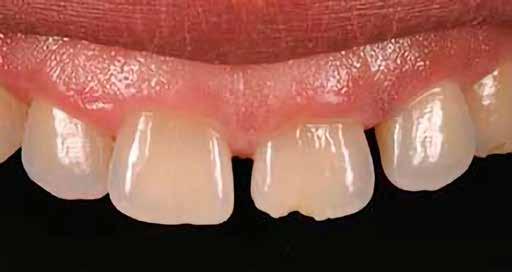

Egy 30 éves, negatív kórtörténettel rendelkező beteg azzal a kéréssel fordult hozzánk, hogy cseréljük ki az UR1 traumája után, 10 évvel korábban készült korábbi kompozit-helyreállítást.

A klinikai vizsgálat során az UR1 reagál a viabilitási tesztre, és az ugyanazon a napon készült röntgenfelvételen nem mutat periapikális elváltozásokat (1. ábra).

Az UR1 elszíneződött, és palatálisabb helyzetben van, mint az ellenoldali központi UL1 (2. ábra)

Az esztétikai elemzés a gingivális zenit aszimmetriáját mutatja az UR1 és az UL1 között. Parodontális szonda segítségével, plexusérzéstelenítés után, az IA

típusú funkcionális hám megváltozott passzív erupcióját igazoljuk Coslet és mtsai. osztályozása szerint (3. ábra)

A lehető legkonzervatívabb helyreállító kezelés elvégzése érdekében a páciensnél, figyelembe véve a megtartott fogelem korát és vitalitását, a tervezés és a diagnosztikai felviaszolás után a közvetlen kompozit-helyreállítás elvégzése mellett döntünk.

A kezelés napján, helyi plexusérzéstelenítést követően, az UR1-et kofferdámmal izoláljuk, kiterjesztve az izolációt az első premolárisokra (4. ábra)

Ezt követően eltávolítjuk a törött kompozt-helyreállítást, és az előkészített fogon rövid ferdére preparálást készítünk, majd az UR1 teljes felületén homokfúvást végzünk 27 μm-es alumínium-oxid porral (5. ábra)

A megváltozott passzív erupció korrigálása érdekében úgy döntöttünk, hogy a fog kiemelkedési profilját a vesztibuláris kidomborodás hangsúlyozásával és az ellenoldali elemmel való szimmetriára törekvéssel újra létrehozzuk. Erre a célra

egy előre megformázott fémmatricát használunk, amelyet két ékkel blokkolunk.

A matrica adaptálása után az adhéziós eljárásokat egy 3 lépéses etch&rinse rendszerrel végezzük. Minden egyes lépést 40 másodperces, UV-fénnyel történő polimerizálás követ (6. ábra)

A vesztibuláris kiemelkedési profilt zománcszínű kompozittal (a TOKUYAMA DENTAL ESTELITE ASTERIA WE termékével) állítjuk helyre (7. ábra).

A diagnosztikai felviaszolás szilikonindexének elkészítése után a palatinális falat zománcszínű kompozittal (a TOKUYAMA DENTAL ESTELITE ASTERIA WE termékével) helyreállítjuk (8. ábra)

Ezt követően helyreállítjuk a dentin anatómiáját a mamelonok reprodukálásával egy átlátszatlan dentinszínű kompozittal (a TOKUYAMA DENTAL ESTELITE SIGMA QUICK OA2 termékével); ez a szín alapvető fontosságú lesz a diszkromatikus elem színének korrigálásához is (9. ábra) Világoskék és fehér hatású árnyalatokat (a TOKUYAMA

DENTAL ESTELITE COLOR termékét) alkalmazunk az opá-

losság emulálásához az incizális területen (10. ábra)

A rétegezést egy zománcszín (a TOKUYAMA DENTAL ESTELITE ASTERIA WE terméke) használatával végezzük a vesztibulárisban, egyszeri hozzáadással. A vesztibuláris felületet háromdimenziós térfogatban modellezzük és vezéreljük annak érdekében, hogy a lehető legkevesebb végső kiigazítás legyen. Ezután 20 másodpercig polimerizáljuk, majd 40 másodpercig polimerizáljuk vesztibulárisan és palatinálisan, miután bevontuk őket gliceringéllel a kompozit hibrid rétegének elkerülése érdekében (11. ábra).

A finírozási és polírozási eljárásokat úgy végezzük, hogy megpróbáljuk emulálni az UL1 átmenő vonalait (12–13. ábra)

A pácienst 21 nap (14–15. ábrák) és 12 hónap (16. ábra) után ismét ellenőrizzük, hogy értékeljük az esztétikai eredményt a forma és a szín tekintetében.